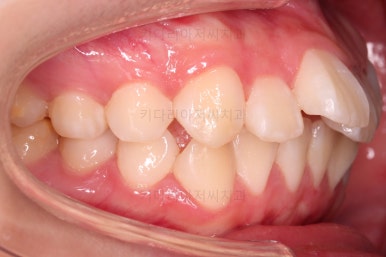

초진 시, 입 안의 모습입니다.

공간이 부족해서 앞니가 앞으로 많이 뻐드러졌고, 삐뚤한 양상 때문에 덧니가 되었네요.

어금니 맞물림도 좋지 못한 앵글씨 2급 부정교합 상태였어요.

이 분은 치아배열, 악궁형태, 입술형태 및 양상, 치아표면과 씹는 면의 형태, 기타 등등으로 봤을 때 호흡기 문제가 있을 가능성이 매우 높았어요.